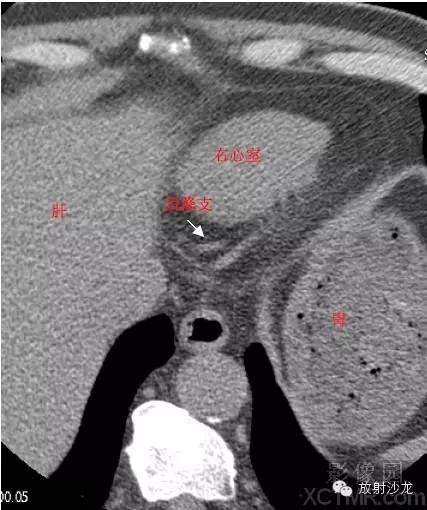

RV -Right Ventricle右心室

ConusBranch右动脉圆锥支